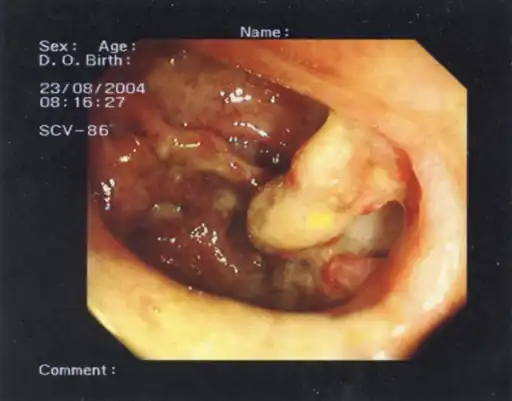

-

Toxic megacolon (and an appendiceal-sigmoid fistula). -

Toxic megacolon in a patient with ulcerative colitis: The patient subsequently underwent a colectomy.